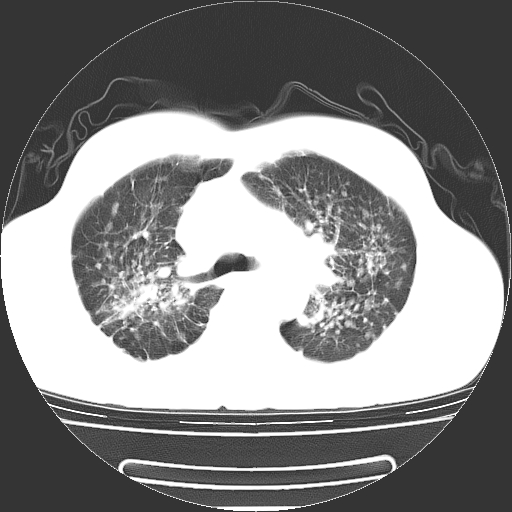

以下是引用yangyudong333在2008-4-29 5:38:00的发言:[br]比较典型的矽肺结节.支持[br]诊断依据:[br] 1.x线表现:[br] ①典型矽肺为多发直径 1~3mm 小结节,即矽结节,由胶原纤维和硅尘构成,可融合成团块,好发于上肺。[br] ②团块周围常有肺大泡。[br] ③胸内淋巴结增大、钙化。如肺门淋巴结呈蛋壳样钙化有助于与其他尘肺区别。[br] ④胸膜常广泛粘连、增厚。[br] 2.ct表现[br] ①两肺散在大小较为一致的小结节影,其密度较高,边界清楚。[br] ②小结节可融合为较大团块影,直径约 1cm ,甚至可达 10cm以上,易发生在上叶。[br] ③小结节周围常并有小叶中心气肿或弥漫性肺气肿。

以下是引用liuyue在2008-4-28 22:30:00的发言:[br]比较典型的矽肺结节.[br]请结合临床及化验除外矽肺合并肺结核之可能.